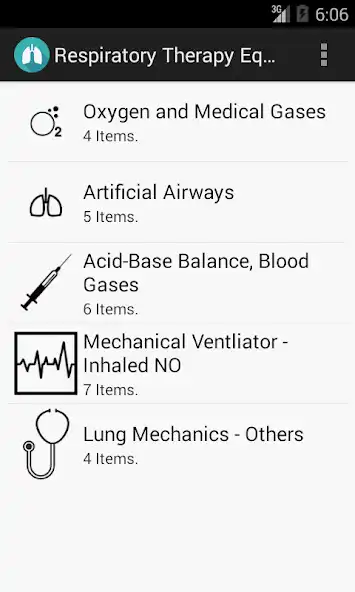

Application developed specifically to assist Respiratory Therapists in their daily work routines around the hospital.

Provides an easy access to equations and charts used by Respiratory Therapists in the palm of your hand.